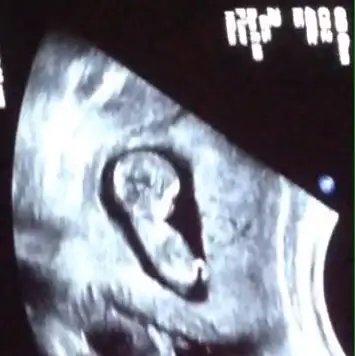

Canım sen daha iyi anlıyosun bu nub olayından benimkine de bi baksanda tahminde bulunsann lütfennnnn :)

canım ben çok net fotolarda anlayabiliyorum. Çok net anlamıyorum.

gözün aydın canım. Allah tamamını erdirsin. İkili test için kan verdin onun dışında renkli ultrasonda da bakıldı mı. bende cumartesi ikili test için randevum varda. merak ediyorum.Az önce doktordan geldik kızlar ikili tarama testimiz yapıldı, çok şükür ense kalınlığımız 1,2 gayet iyi dedi doktorumuz cinsiyeti söylemedi maalesef hadi siz bi tahminde bulunun bizim için![]()

Annem benimm ne kadar da tatlı maşallah :)nubu görünmüyor canım yorum yapmayim o yüzden....Az önce doktordan geldik kızlar ikili tarama testimiz yapıldı, çok şükür ense kalınlığımız 1,2 gayet iyi dedi doktorumuz cinsiyeti söylemedi maalesef hadi siz bi tahminde bulunun bizim için![]()

Kiz benceKizlar bakarmisiniz. Doktor 11hafta 1gunluk diyor ama ben yumurtlama günümü bildiyim Have you send?için 12hafta 2gunluk die hesapladim hep. Resme bakarmisiniz kimdir sizcə bu çocuEki Görüntüle 1547074 k?? Doktor tahmin bilə yapmadi

Erkek12+3 sizden tahmin almak istiyorum

cevapladiginiz icin tesekkurler. siz nubu gordunuzmu ? nuba goremi tahmin etdiniz? bir arkadas burda nubun belli olmadigini kafa kemigine gore tahmin yapdiKiz bence